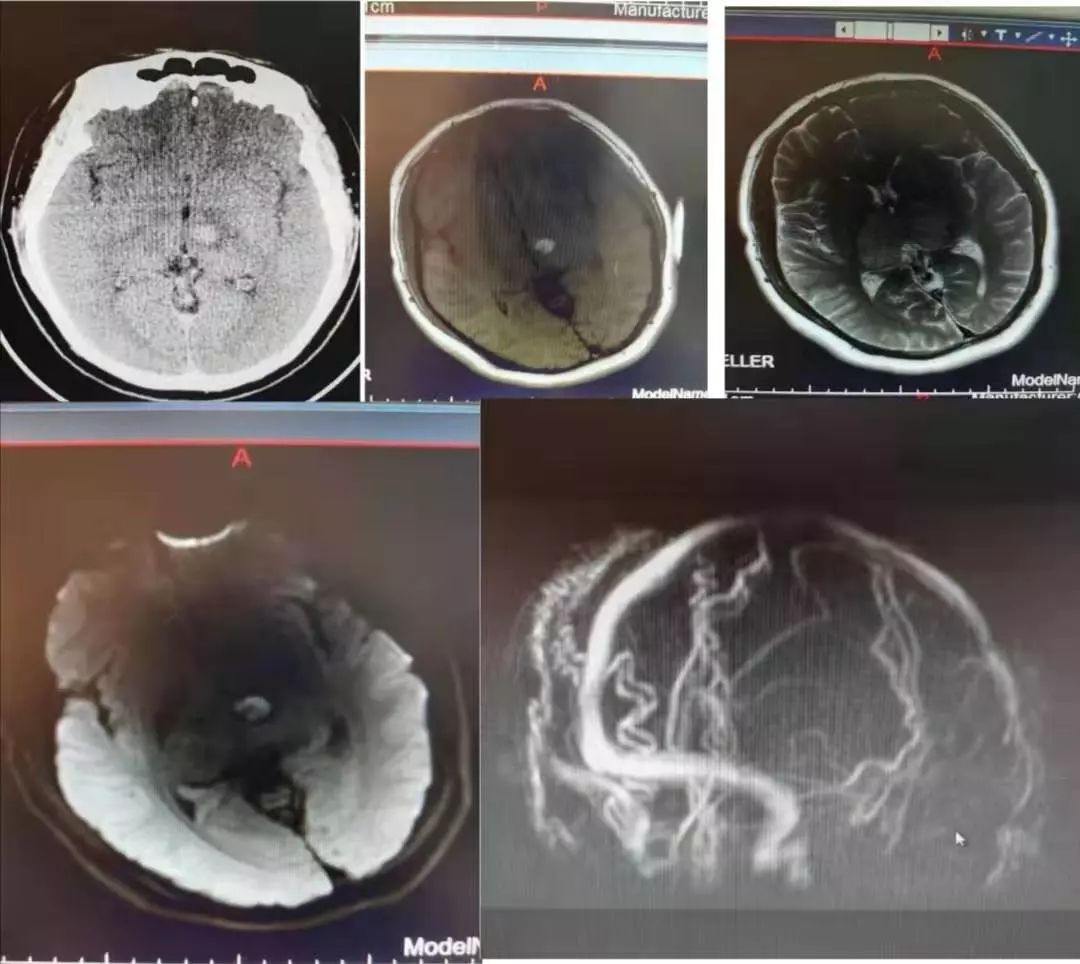

病例8

中年男性,突发言语不清。

诊断脑栓塞是没有问题的,重点在于栓子来源的筛查。对于病因,群里老师们的总结已经很有一套;对于这个患者,却画风突变,1年后癫痫发作再次入院,颅脑影像如下:

答案:心脏黏液瘤。

近期群内发过一个手术切除后的心脏黏液瘤标本视频,直观生动印象深刻。心脏黏液瘤是最常见的原发性心脏肿瘤,占原发性心脏肿瘤的 50% 以上,70%发生在左心房。心脏黏液瘤具有良性特征,但因其质脆易碎易脱落进入血液循环并转移至全身其他部位,产生不良后果,心脏黏液瘤可具有以下3种心脏外转移的病理学过程:脑血管梗死引起缺血性卒中,实质性肿瘤定植、转移和肿瘤性多发性脑动脉瘤形成、伴或不伴出血。

1894年Marchand首次报道心脏黏液瘤导致多发性颅内动脉瘤形成,它是心脏黏液瘤的中枢神经系统并发症之一。心脏黏液瘤导致多发性颅内动脉瘤形成的可能机制有:(1)血管损伤理论:心脏黏液瘤细胞栓子脱落,经体循环进入脑血管,脑动脉末梢管腔直径小,瘤栓附着于微小动脉壁上,导致血管内皮损伤、瘢痕形成,引起颅内动脉瘤形成;(2)肿瘤定植理论:肿瘤细胞进入脑血管系统后,仍可以保持活力并在局部定植生长。肿瘤组织破坏血管壁,甚至血管壁整个基层均被肿瘤组织破坏、替代,这样可使得其在造影时不仅像真的动脉瘤一样呈瘤样扩张,还有造影剂明显滞留的表现。定植在脑血管内壁的肿瘤细胞有不同的生物学行为,不同的生长速度、方式,既可处于生长休眠状态也可最终坏死,这就可以解释迟发性病变以及多样的动脉瘤形态。在以上两种假说中,脑梗死事件都会发生。而多数学者赞同肿瘤定植理论,有文献报道在组织病理学研究中已经证明了动脉瘤壁中含有活性黏液瘤细胞的增殖及其对内弹力层的侵袭破坏。